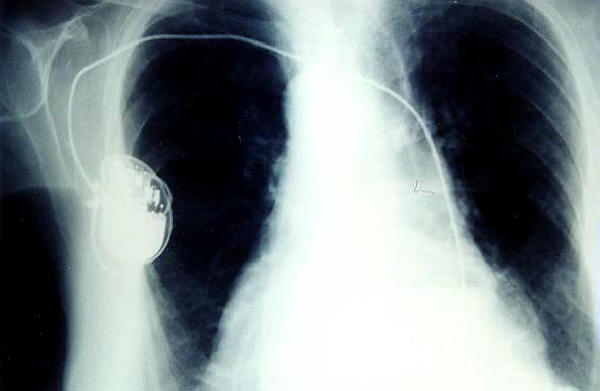

Marcapasos